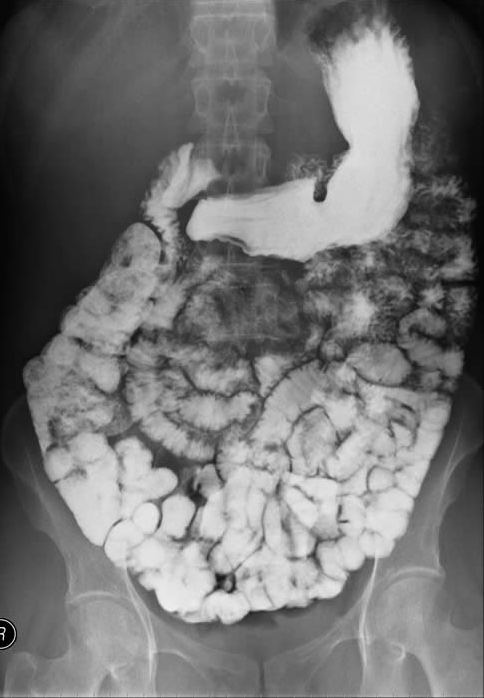

황산 바륨은 X선을 투과하지 않는 성질 덕분에 엑스레이나 소화관 조영 검사에 사용되는 조영제로도 활용된다. 의료용 조영제로는 2004년에 약 1,750만 명이 사용한 것으로 추정된다.

현탁액 형태의 황산 바륨은 X-ray 영상 촬영을 위한 방사선 조영제로 자주 사용된다. 흔히 "바륨 식사"라고 불리는 위장관 영상 촬영에 주로 사용되며, 경구 투여하거나 관장을 통해 투여한다. 굵은 우유와 같은 용액에 미세 입자가 들어 있는 현탁액 형태로 사용된다. 중금속인 바륨의 수용성 화합물은 독성이 강하지만, 황산 바륨은 낮은 용해도 덕분에 인체에 흡수되지 않고 배출되어 안전하다. 또한, 과거에 사용된 토로트라스트와 달리 체내에서 쉽게 제거된다. 바륨은 원자 번호 (''Z'' = 56)가 높아 X-선을 효과적으로 흡수한다.

조영제는 X선을 잘 흡수하기 때문에, 황산 바륨을 내복하여 소화관의 모양을 X선으로 촬영할 수 있게 한다.[3]